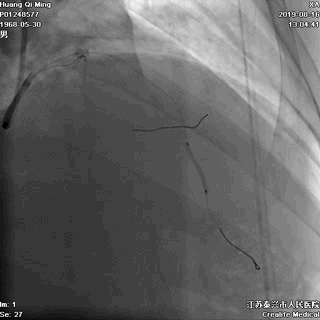

LAD PCI过程

导丝通过病变抵达血管远段

8atm,2.0*20球囊行PTCA

8atm,2.0*10 切割球囊对斑块进行切割

16atm,NC球囊对斑块进行预处理

2.0*25 药物洗脱球囊,8atm*60秒释放药物

2.5*25 药物洗脱球囊,8atm*60秒释放药物

术后即刻效果满意